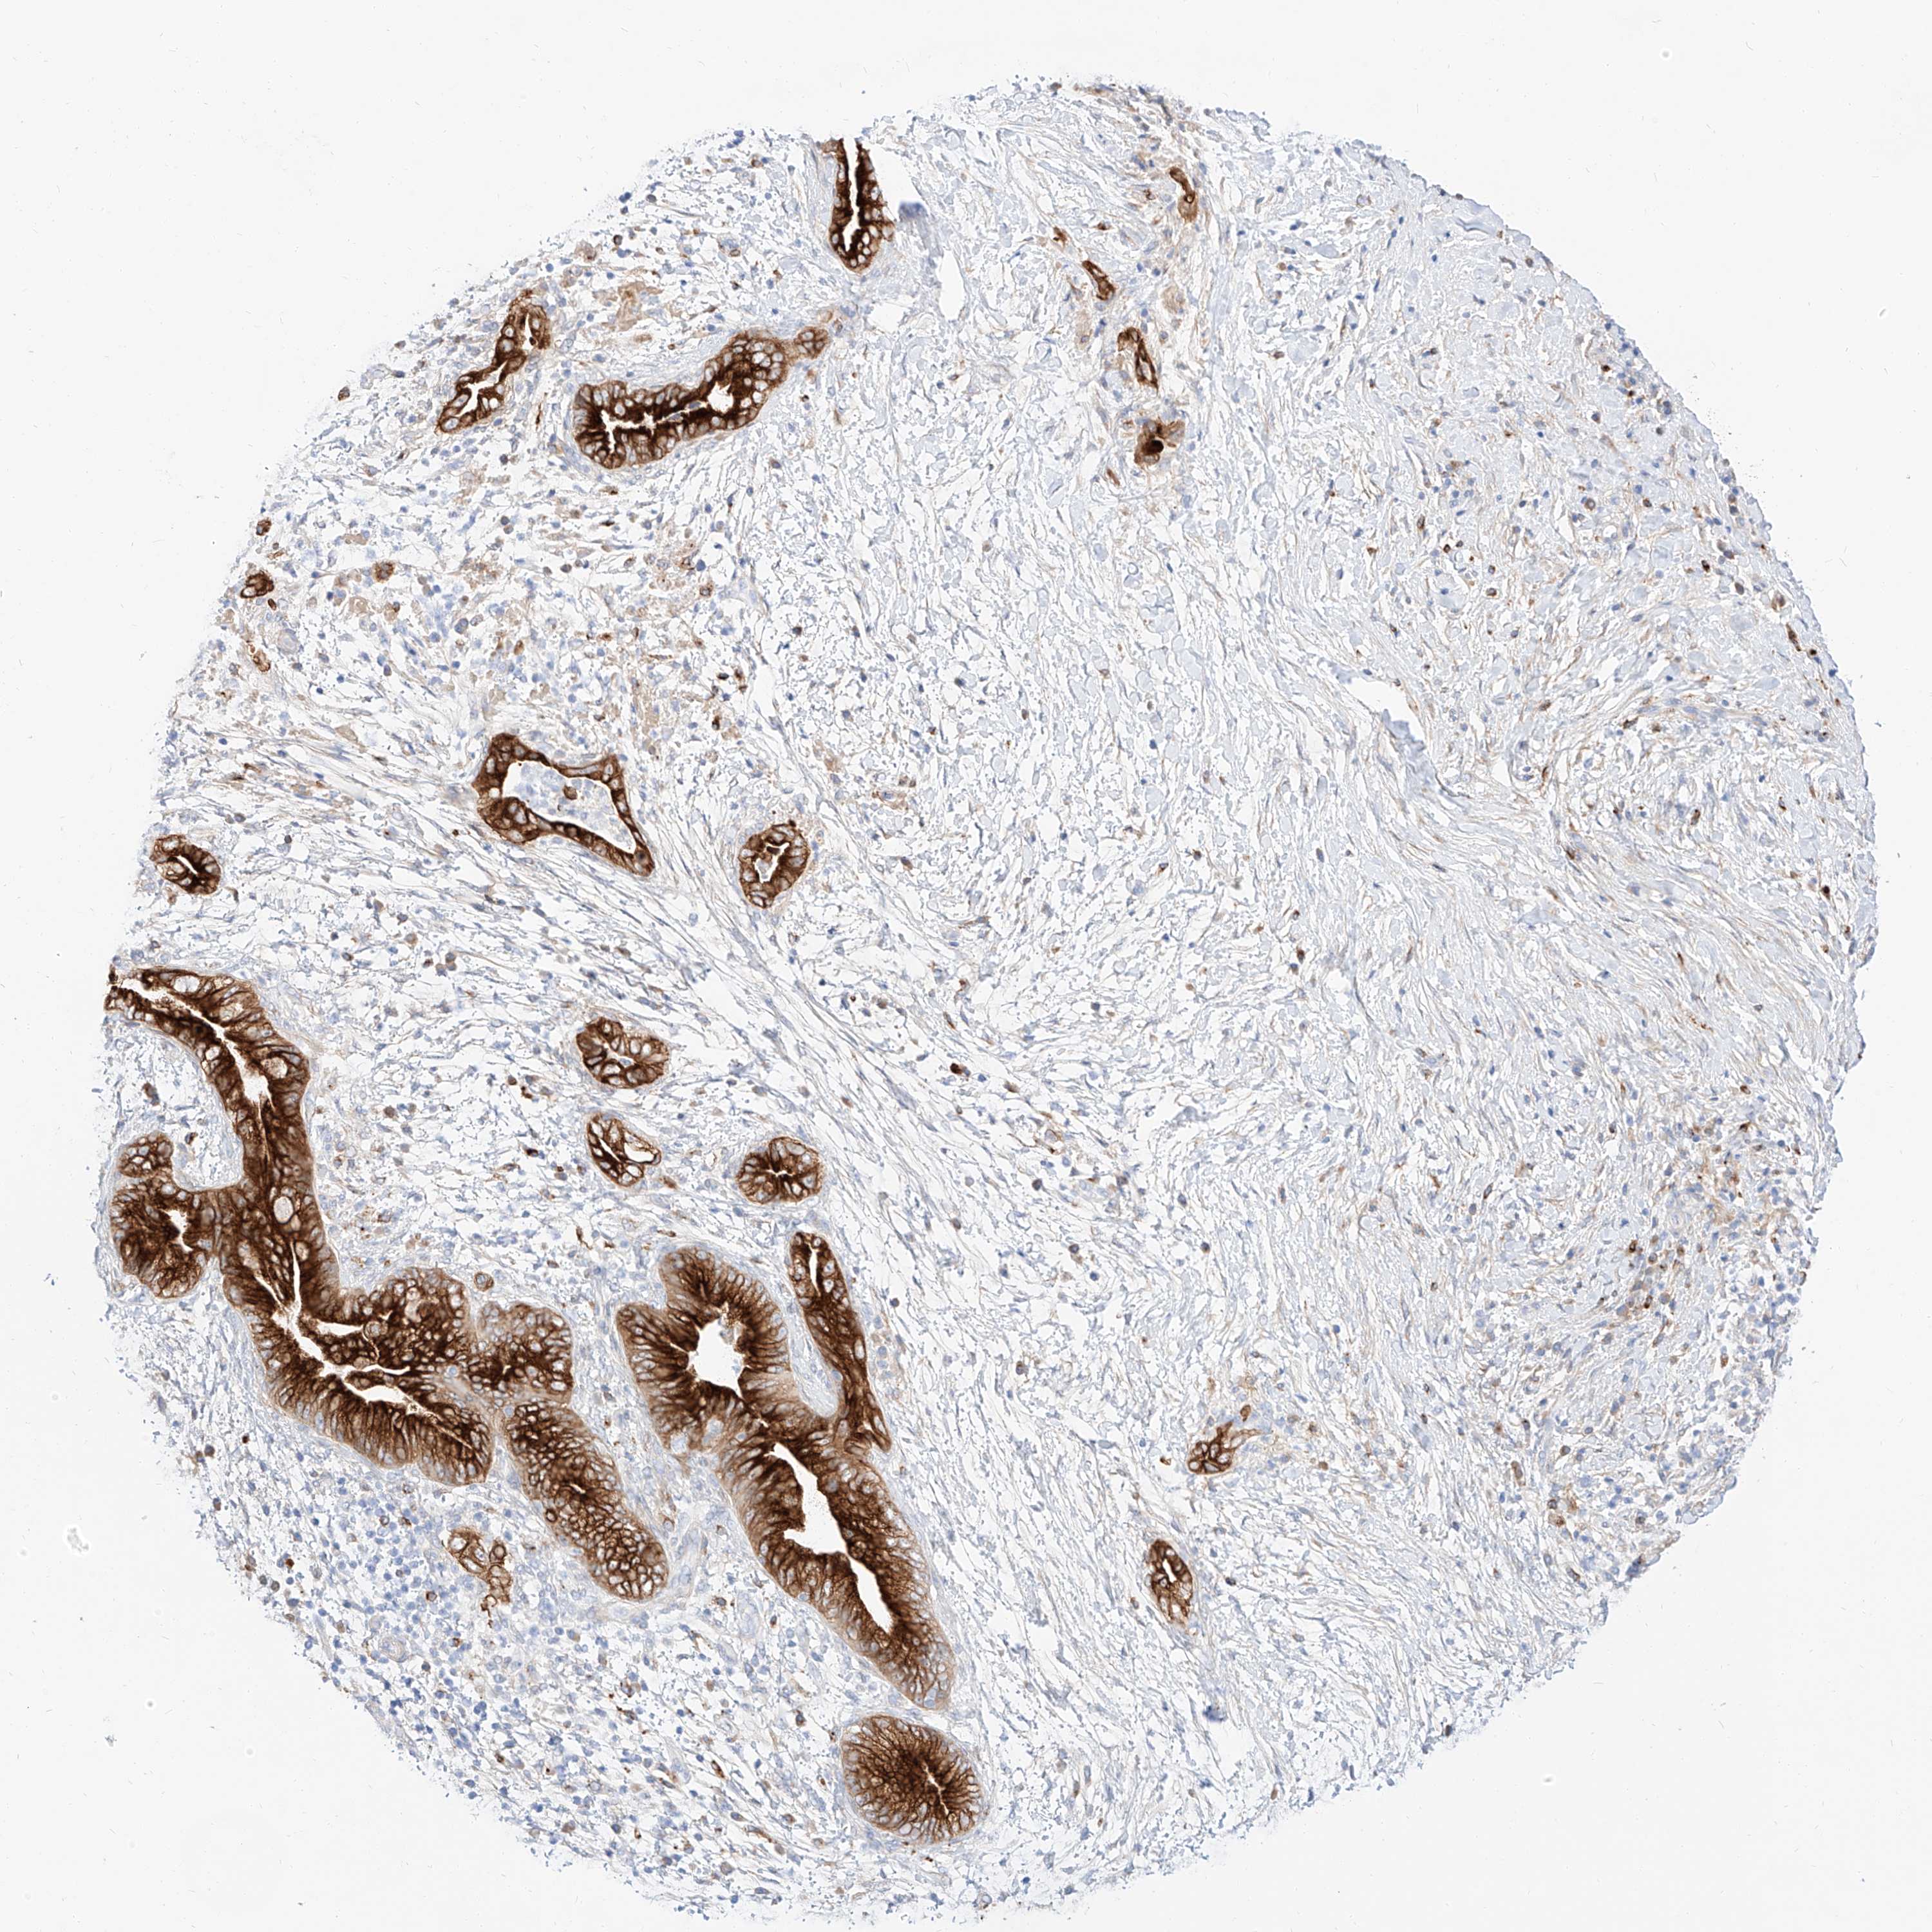

PANCREATIC CANCER - Protein expressioni

A mouse-over function shows sample information and annotation data. Click on an image to view it in a full screen mode. Samples can be filtered based on level of antibody staining by selecting one or several of the following categories: high, medium, low and not detected. The assay and annotation is described here.

Note that samples used for immunohistochemistry by the Human Protein Atlas do not correspond to samples in the TCGA dataset.

Antibody stainingi

Antibody staining in the annotated cell types in the current human tissue is reported as not detected, low, medium, or high, based on conventional immunohistochemistry profiling in selected tissues. This score is based on the combination of the staining intensity and fraction of stained cells.

Each image is clickable and will lead to virtual microscopy that enables deeper exploration of all samples and also displays staining intensity scores, fraction scores and subcellular localization as well as patient and tissue information for each sample.

Antibody HPA029712

Antibody HPA029713

Staining

High

Medium

Low

Not detected

Intensity

Strong

Moderate

Weak

Negative

Quantity

>75%

75%-25%

<25%

None

Location

Nuclear

Cytoplasmic/membranous

Cytoplasmic/membranous,nuclear

Adenocarcinoma, NOS